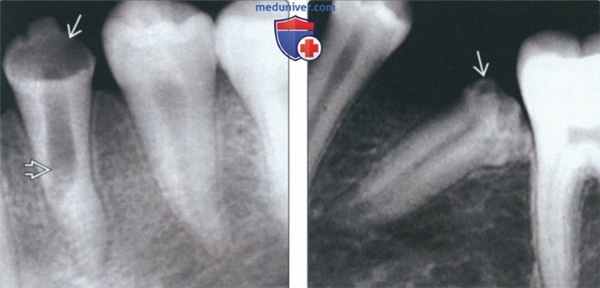

• Лучший диагностический критерий:

о Отсутствие эмали и неровная поверхность дентина изолированного зуба

• Локализация:

о Наиболее часто премоляры, реже-любой другой зуб

о Постоянные моляры никогда не поражаются (нет предшественников)

• Задние зубы:

о Деформация коронки с отсутствием эмали

о Неровная поверхность дентина

• Передние зубы:

о Горизонтальные гипопластические тяжи низкой плотности поперек коронки зуба

о Часто имеется связь с травмой

• Лучший метод визуализации:

о Периапикальная рентгенография

о Ищите расширение верхушечного пространства периодонтальной связки, рарефицирующий остеит или конденсирующий остеит как следствие восприимчивости зубов к кариесу с последующим возникновением патологии пульпы

(Слева) На периапикальной рентгенограмме у пациента с дисплазией Тернера определяется утрата тканей коронки первого премоляра нижней челюсти слева. Расширение пульпового канала может быть обусловлено внутренней резорбцией или удалением избыточного количества тканей во время вмешательства на канале.

(Справа) На периапикальной рентгенограмме у пациента с дисплазией Тернера визуализируется импактный второй премоляр нижней челюсти. Обратите внимание на неровный край эмали и дентина коронки.